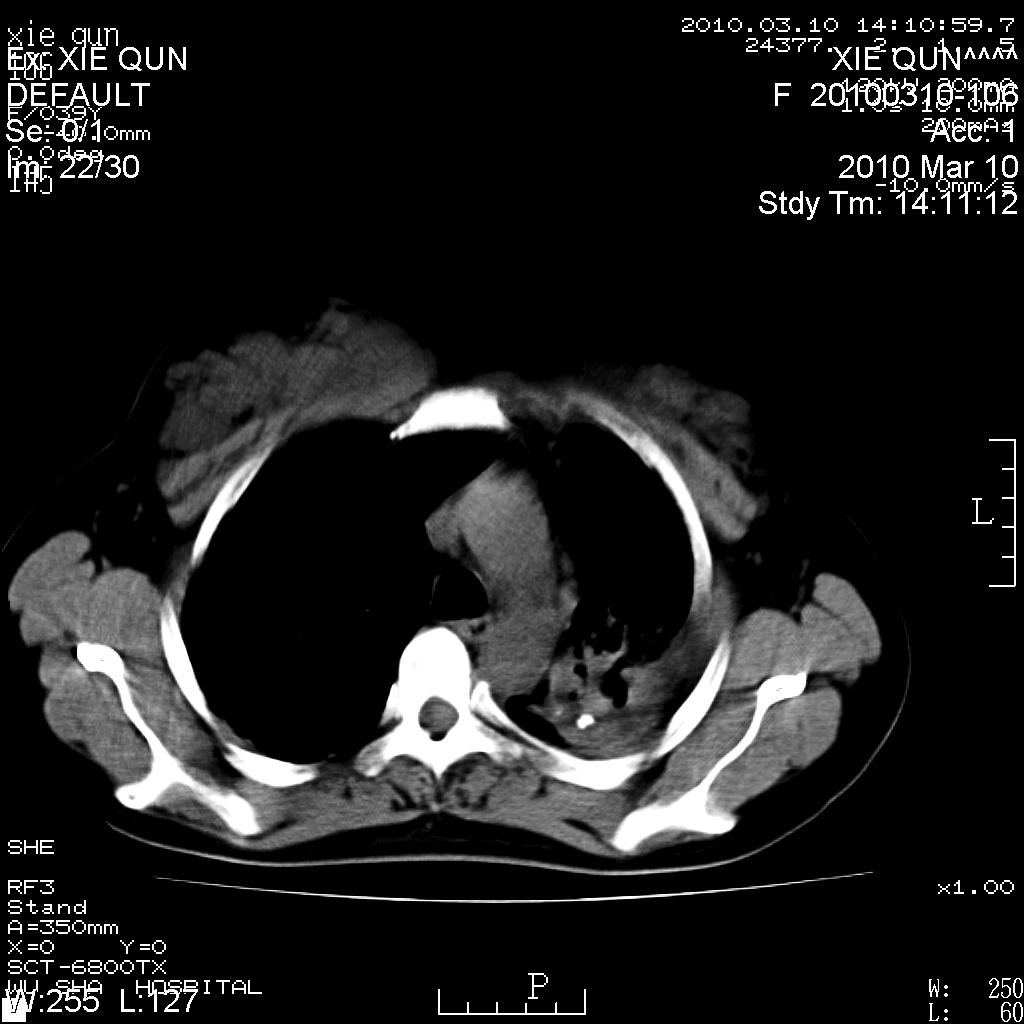

以下是引用心路寻觅在2010-3-24 17:28:00的发言:[br]两肺继发性tb左上肺空洞形成,建议痰检明确诊断。

以下是引用随光逐影在2010-3-24 19:19:00的发言:[br]两肺继发性结核并左上肺上叶空洞形成。